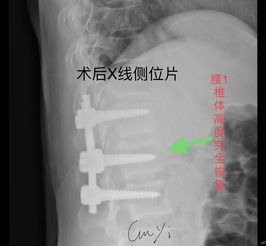

手術(shù)大致分為后路、側(cè)路、前路3個(gè)途徑。以往的手術(shù)常選擇后路的椎板減壓、探查+內(nèi)固定,但后來(lái)逐步發(fā)現(xiàn)后路手術(shù)在很多情況下難以恢復(fù)脊柱的正常形態(tài)及穩(wěn)定性,對(duì)來(lái)自前方的壓迫不易解除,長(zhǎng)期隨訪又發(fā)現(xiàn)了內(nèi)固定失效、融合失敗、脊柱不穩(wěn)、畸形愈合等情況;而且脊柱的后路內(nèi)固定術(shù)須通過(guò)前柱的承重來(lái)實(shí)現(xiàn)其張力帶作用,抵抗?fàn)繌埩蛷澢?,因此,前方支撐系統(tǒng)不可或缺。

由于X線檢查技術(shù)的進(jìn)步,特別是CT、MRI的應(yīng)用,使人們確信脊柱骨折中脊髓神經(jīng)所受的打擊或壓迫大多來(lái)自硬脊膜前方,施行前路減壓術(shù)有了肯定的理由。但是前路手術(shù)因?yàn)樯婕靶?、腹腔臟器及重要血管等結(jié)構(gòu)較多,手術(shù)難度較大,術(shù)后并發(fā)癥多,不僅對(duì)病人的全身、局部情況要求較高,而且也要求醫(yī)生掌握扎實(shí)的基礎(chǔ)理論和豐富的臨床經(jīng)驗(yàn),具備熟練的手術(shù)技巧。

不少醫(yī)生因此裹足不前,致使一些適合前路手術(shù)的病例被施行了后路手術(shù)。泉州市第一醫(yī)院骨科在胸腰椎骨折脫位伴截癱的診療上積累了豐富的經(jīng)驗(yàn),近年來(lái)逐步開(kāi)展前路手術(shù),取得了良好療效,技術(shù)日趨簡(jiǎn)潔、熟練。

胸腰椎前路內(nèi)固定技術(shù)的應(yīng)用使病灶得到清除、脊髓獲得減壓、脊柱得到即刻穩(wěn)定,這樣一方面為病人術(shù)后早期離床活動(dòng)、早期康復(fù)提供了可能性,另一方面也為神經(jīng)功能的保護(hù)或恢復(fù)創(chuàng)造了必要條件;其合理性和臨床效果逐步得到了公認(rèn)。 但前路手術(shù)無(wú)法探查脊髓、馬尾損傷的情況并給于必要的處理,因此把握好前路手術(shù)的適應(yīng)證是臨床取效的關(guān)鍵,以下幾點(diǎn)基本達(dá)成共識(shí):胸腰椎骨折或骨折脫位伴不全癱,確證在硬脊膜前方有壓迫存在;經(jīng)過(guò)脊髓造影、MRI或臨床神經(jīng)學(xué)體征可判斷,除硬膜前受壓外,馬尾、脊髓本身并無(wú)需探查及修復(fù)時(shí),必須致力于前路減壓;脫位已超過(guò)2~3周者,后路手術(shù)已難以復(fù)位者;若伴不全癱需行減壓術(shù),亦宜選用前路減壓。